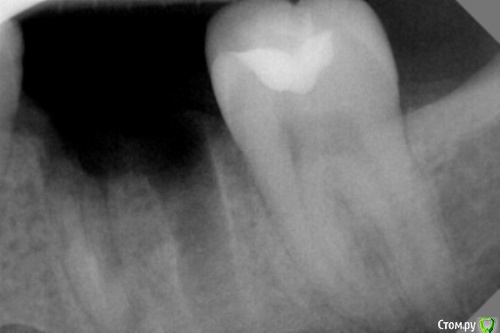

dr.Dre Опубликовано 2 февраля, 2017 Поделиться Опубликовано 2 февраля, 2017 Добрый день уважаемые коллеги ,не могу никак удалить медиальный корень,как быть ?Как вы поступаете в таких ситуациях? Ссылка на комментарий

алекс 100 Опубликовано 2 февраля, 2017 Поделиться Опубликовано 2 февраля, 2017 Если перегородка не нужна-элеватор "на себя".Хотя по снимку странно что возникла сложность с удалением. 1 Ссылка на комментарий